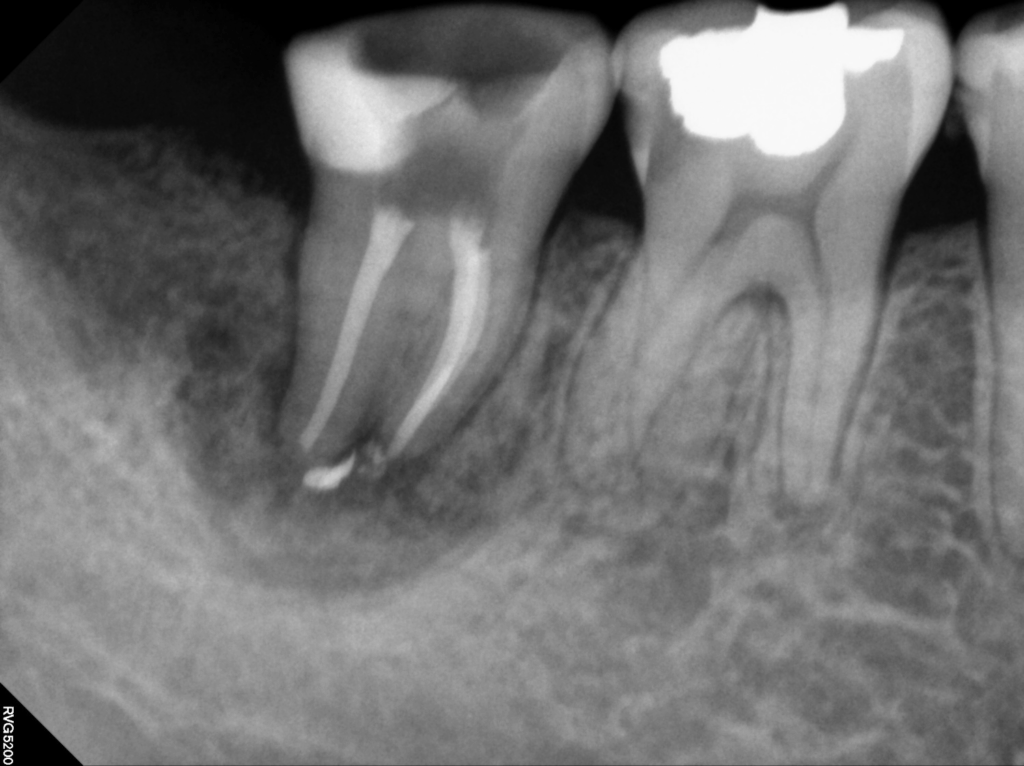

24.10.17

치료 후 촬영한 사진에서는 이전과 비교해 변화된 양상을 확인할 수 있습니다.

치근 주변에 보이던 방사선 투과성 부위는 이미 뼈가 흡수된 상태라 회복 속도가 빠르지는 않지만, 그럼에도 불구하고 염증이 상당 부분 가라앉아 회복 방향이 긍정적으로 진행되고 있음을 확인했습니다.

영도치과 서울화이트S치과에서는 이번 재치료 과정에서 근관 내부의 밀봉과 차단을 꼼꼼하게 다시 시행하였고, 그 결과 치아의 흔들림과 불편감이 이전보다 줄어들어 환자분께서도 안정적인 변화를 체감하며 지속적으로 경과 관찰을 이어가고 있습니다.